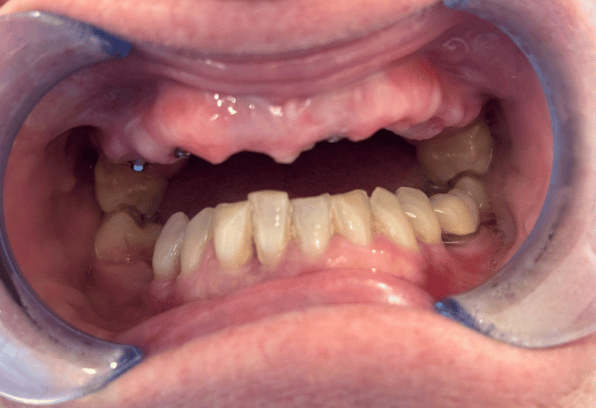

Learn More Before

Before

Read MoreA smile makeover with an implant on the front incisor, bone graft and soft tissue graft. The smile was enhanced with composite bonding to give…